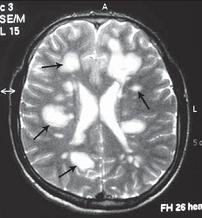

МРТ № 1

На магнитно-резонансной томографии (МРТ) № 1 — шейный отдел позвоночника, в относительно нормальном состоянии.

Шейный отдел позвоночника должен иметь нормально выраженный физиологический лордоз, не должно быть гиполордоза или гиперлордоза, а так же кифотических деформаций.

Ширина спинного мозга: сагиттально > 6–7 мм

1. Сагиттальный размер позвоночного канала на уровне:

СI 21 мм

СII 20 мм

СIII 17 мм

CIV-CVII = 14 мм

2. Высота межпозвонковых пространств:

СII < СIII < СIV < СV < СVII  СVII

3. Ширина спинномозгового канала: поперечный диаметр на уровне ножек: > 20–21 мм